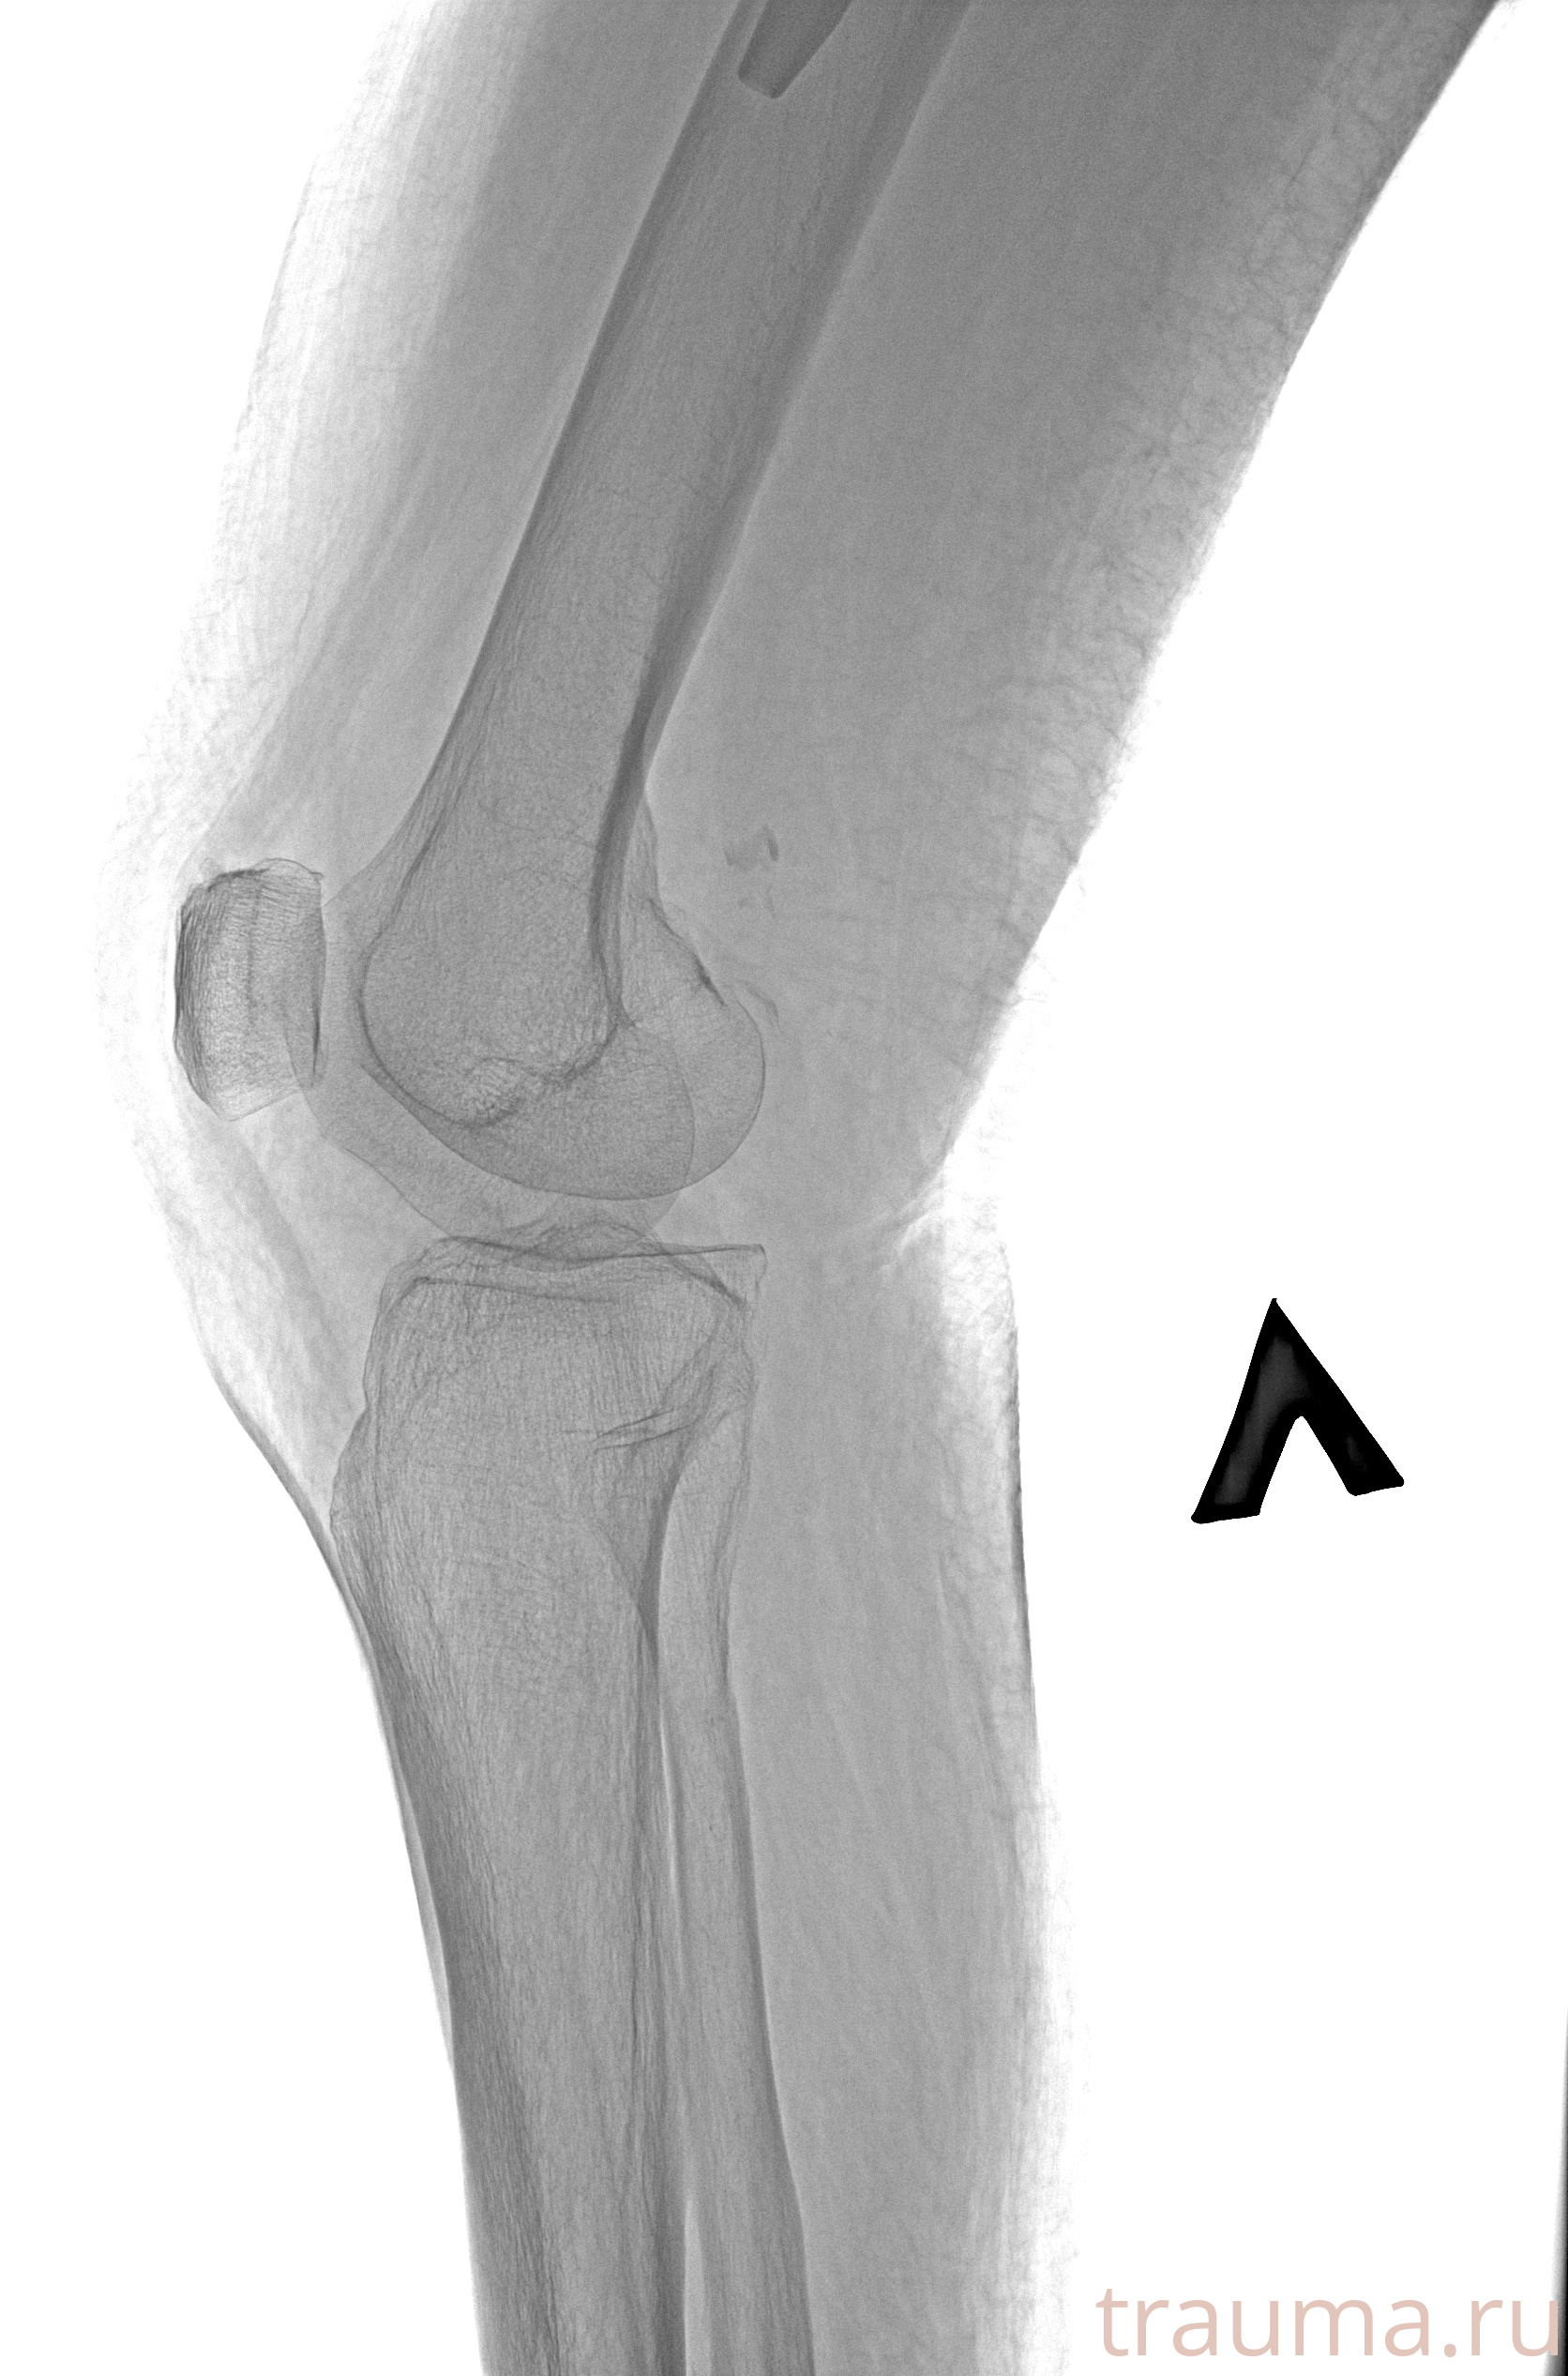

Рентгенограммы

Рентген на дому: по вашему адресу приезжает врач-рентгенолог, травматолог-ортопед с мобильным рентгеновским аппаратом, проводит диагностику травмы или заболевания, делает необходимые рентгенограммы, дает рекомендации по дальнейшему лечению. Получить качественные снимки в домашних условиях возможно благодаря уникальной методике, разработанной МосРентген Центром для института  Склифосовского